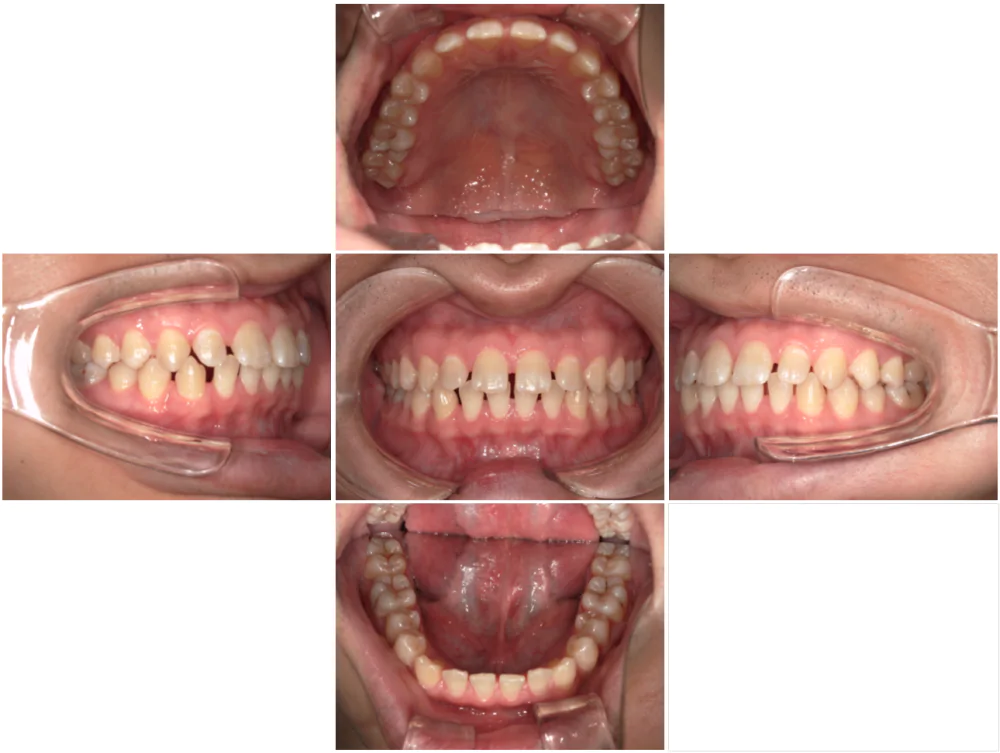

症例5

| 来院時の主訴 | 全体的なガタガタ |

| 医院での対応や適用装置 | 上顎の小臼歯抜歯、ワイヤー矯正にて主訴で |

| 通院期間 | 1年2ヶ月 |

| 通院回数 | 14回 |

| 治療費用総額 | 720,500円(学生割引適応) |

| リスクと副作用 | 矯正治療による歯の移動に伴う痛み、歯根吸収、虫歯 |